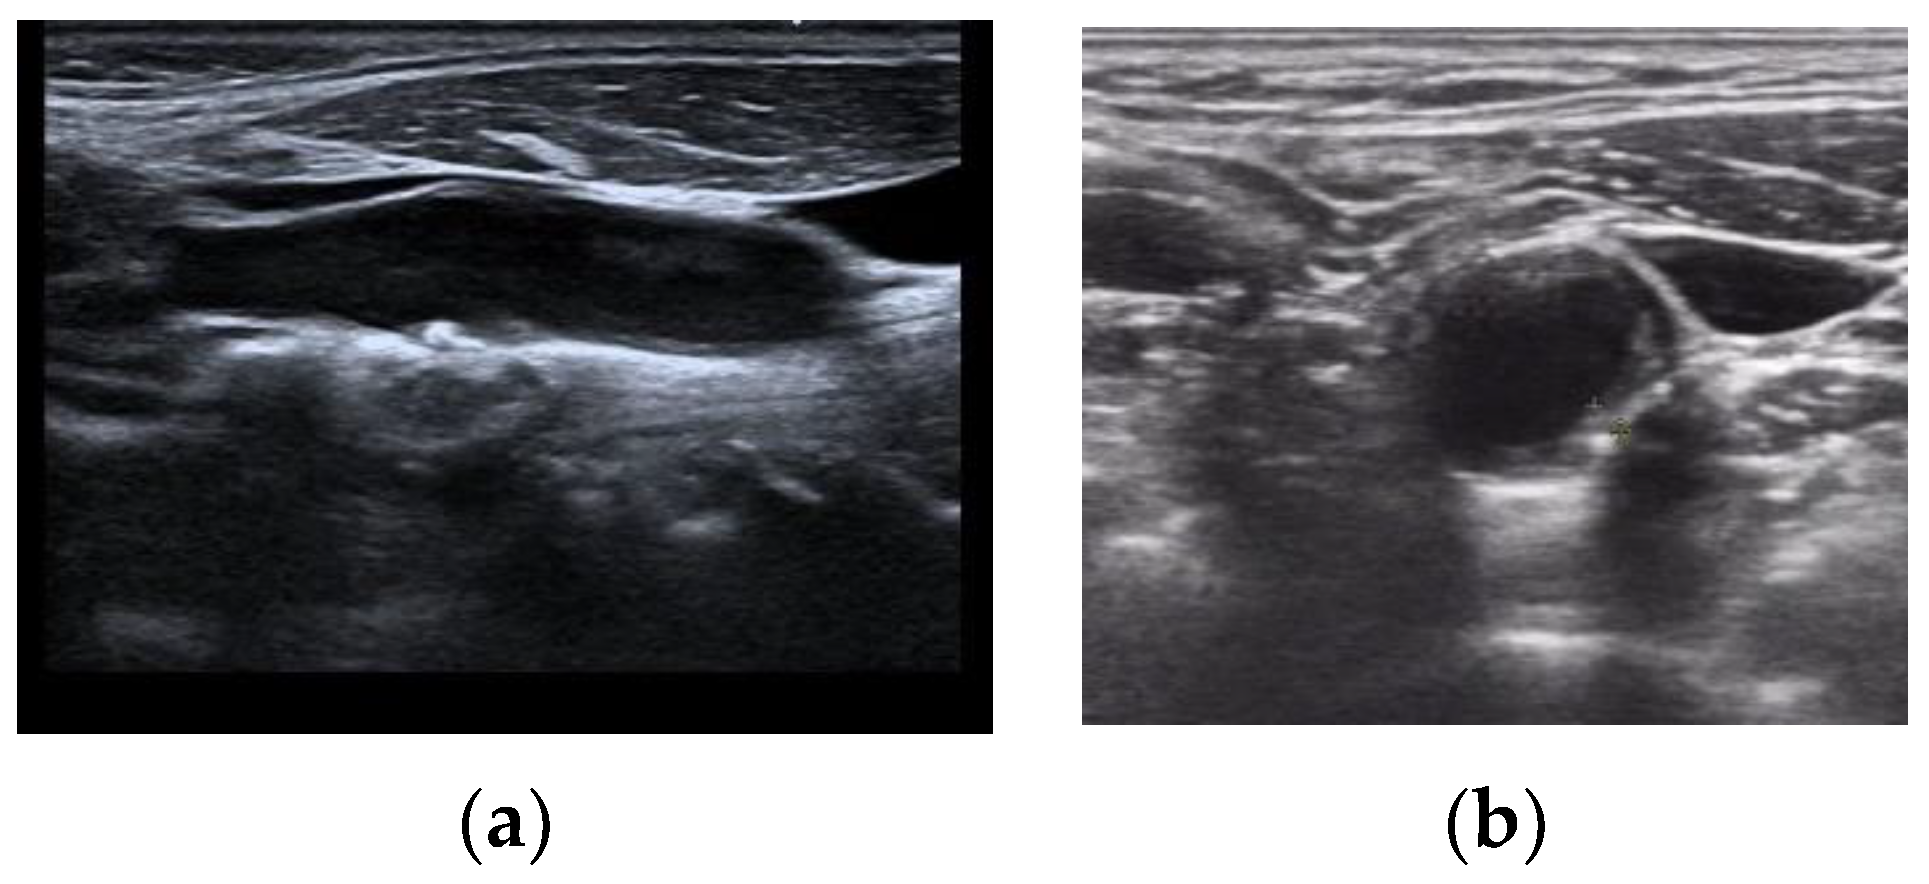

Currently, deep learning has become an effective tool for auxiliary diagnosis and has been progressively applied in the field of plaque diagnosis, showing significant effectiveness in handling plaque data from single medical centers [7,8]. However, the ultrasound plaque image analysis in the real world often involves multiple data sources. These sources, primarily from different medical institutions, contain images with unique feature distributions. To date, there already have been a few studies focusing on multicenter auxiliary diagnostics with a single-source center [9], but research on multi-source centers has not yet been conducted. When expanding from a single source to multiple sources, the complexity of data distribution is significantly higher than in a single-source scenario. The first issue is that not only do the data between the source center and target center show feature differences, but there are also variations between the source centers themselves, which results in the decision boundaries of classifiers designed for single-source centers failing to effectively classify the data from multi-source centers. Secondly, the model faces the issue of inconsistent ultrasound image views, meaning that different source centers contain different views. For example, in the processing of carotid artery plaque images, some source centers might provide datasets that include both longitudinal and transverse images of the carotid artery, while others might offer images from only one angle, as shown in Figure 1. Although this diversity in multi-source center situations adds complexity to the classification task, it also provides a potential for model design—by integrating the “knowledge” of different imaging characteristics and views from different source centers, the model can offer a more enriched set of information sources for the target center.

Figure 1. Carotid ultrasound in different views: (a) is a longitudinal section, while (b) is a transverse section.